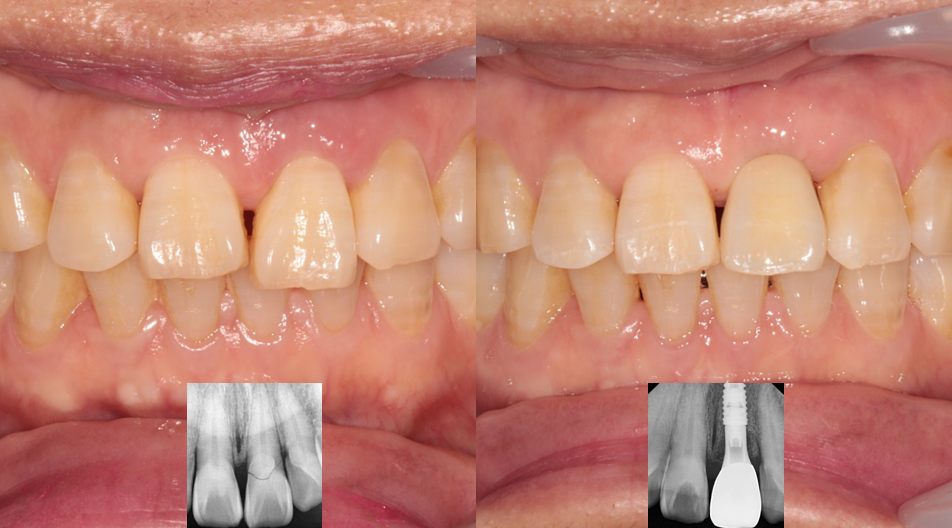

3개월 뒤, 잇몸과 임플란트가 완전히 안정화된 것을 확인하고 최종 보철물을 올려드렸습니다.

주변 자연 치아와 색상, 모양이 조화롭게 어우러지도록 세심하게 제작했습니다.

환자분께서 "어떤 게 임플란트인지 모를 정도로 자연스럽다"며 아주 만족해하셨습니다.